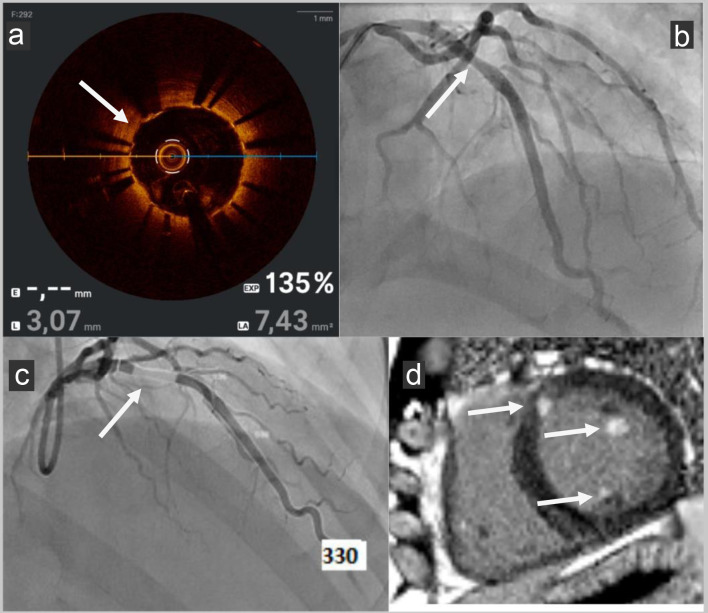

冠状动脉微血管功能障碍(CMD)是经皮冠状动脉介入治疗(PCI)后持续心绞痛的公认原因,特别是在没有心外膜冠状动脉狭窄的患者中。我们报告一个58岁的顶级运动员和世界游泳冠军,尽管成功的PCI治疗左中前降支病变,但持续呼吸困难。随访血管造影光学相干断层扫描显示无支架内再狭窄,支架贴置良好。血管造影衍生的微循环阻力(AMR, Pulse Medical)和心脏磁共振成像显示CMD是潜在的病因。本案例展示了AMR在识别pci后CMD方面的实用性和可行性,并支持其在诊断检查中的使用。

Coronary microvascular dysfunction (CMD) is a recognized cause of persistent angina post-percutaneous coronary intervention (PCI), especially in patients without epicardial coronary stenosis. We report a case of a 58-year-old top-level sportsman and world champion ice swimmer with persistent dyspnea despite successful PCI for a mid-left anterior descending artery lesion. Follow-up angiography with optical coherence tomography showed no in-stent restenosis with good stent apposition. Angiography-derived microcirculatory resistance (AMR, Pulse Medical) and cardiac magnetic resonance imaging revealed CMD as the underlying etiology. This case demonstrates the utility and feasibility of AMR in identifying CMD post-PCI and supports its use in the diagnostic workup.